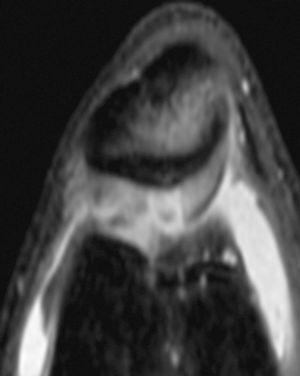

Figura 3 RM. Imagen potenciada en T2 con supresión de grasa. Lesión condral amplia en rótula, faceta externa y cresta condral.

Figura 4 Artroscopia. Lesión condral amplia en rótula, faceta externa y cresta condral.